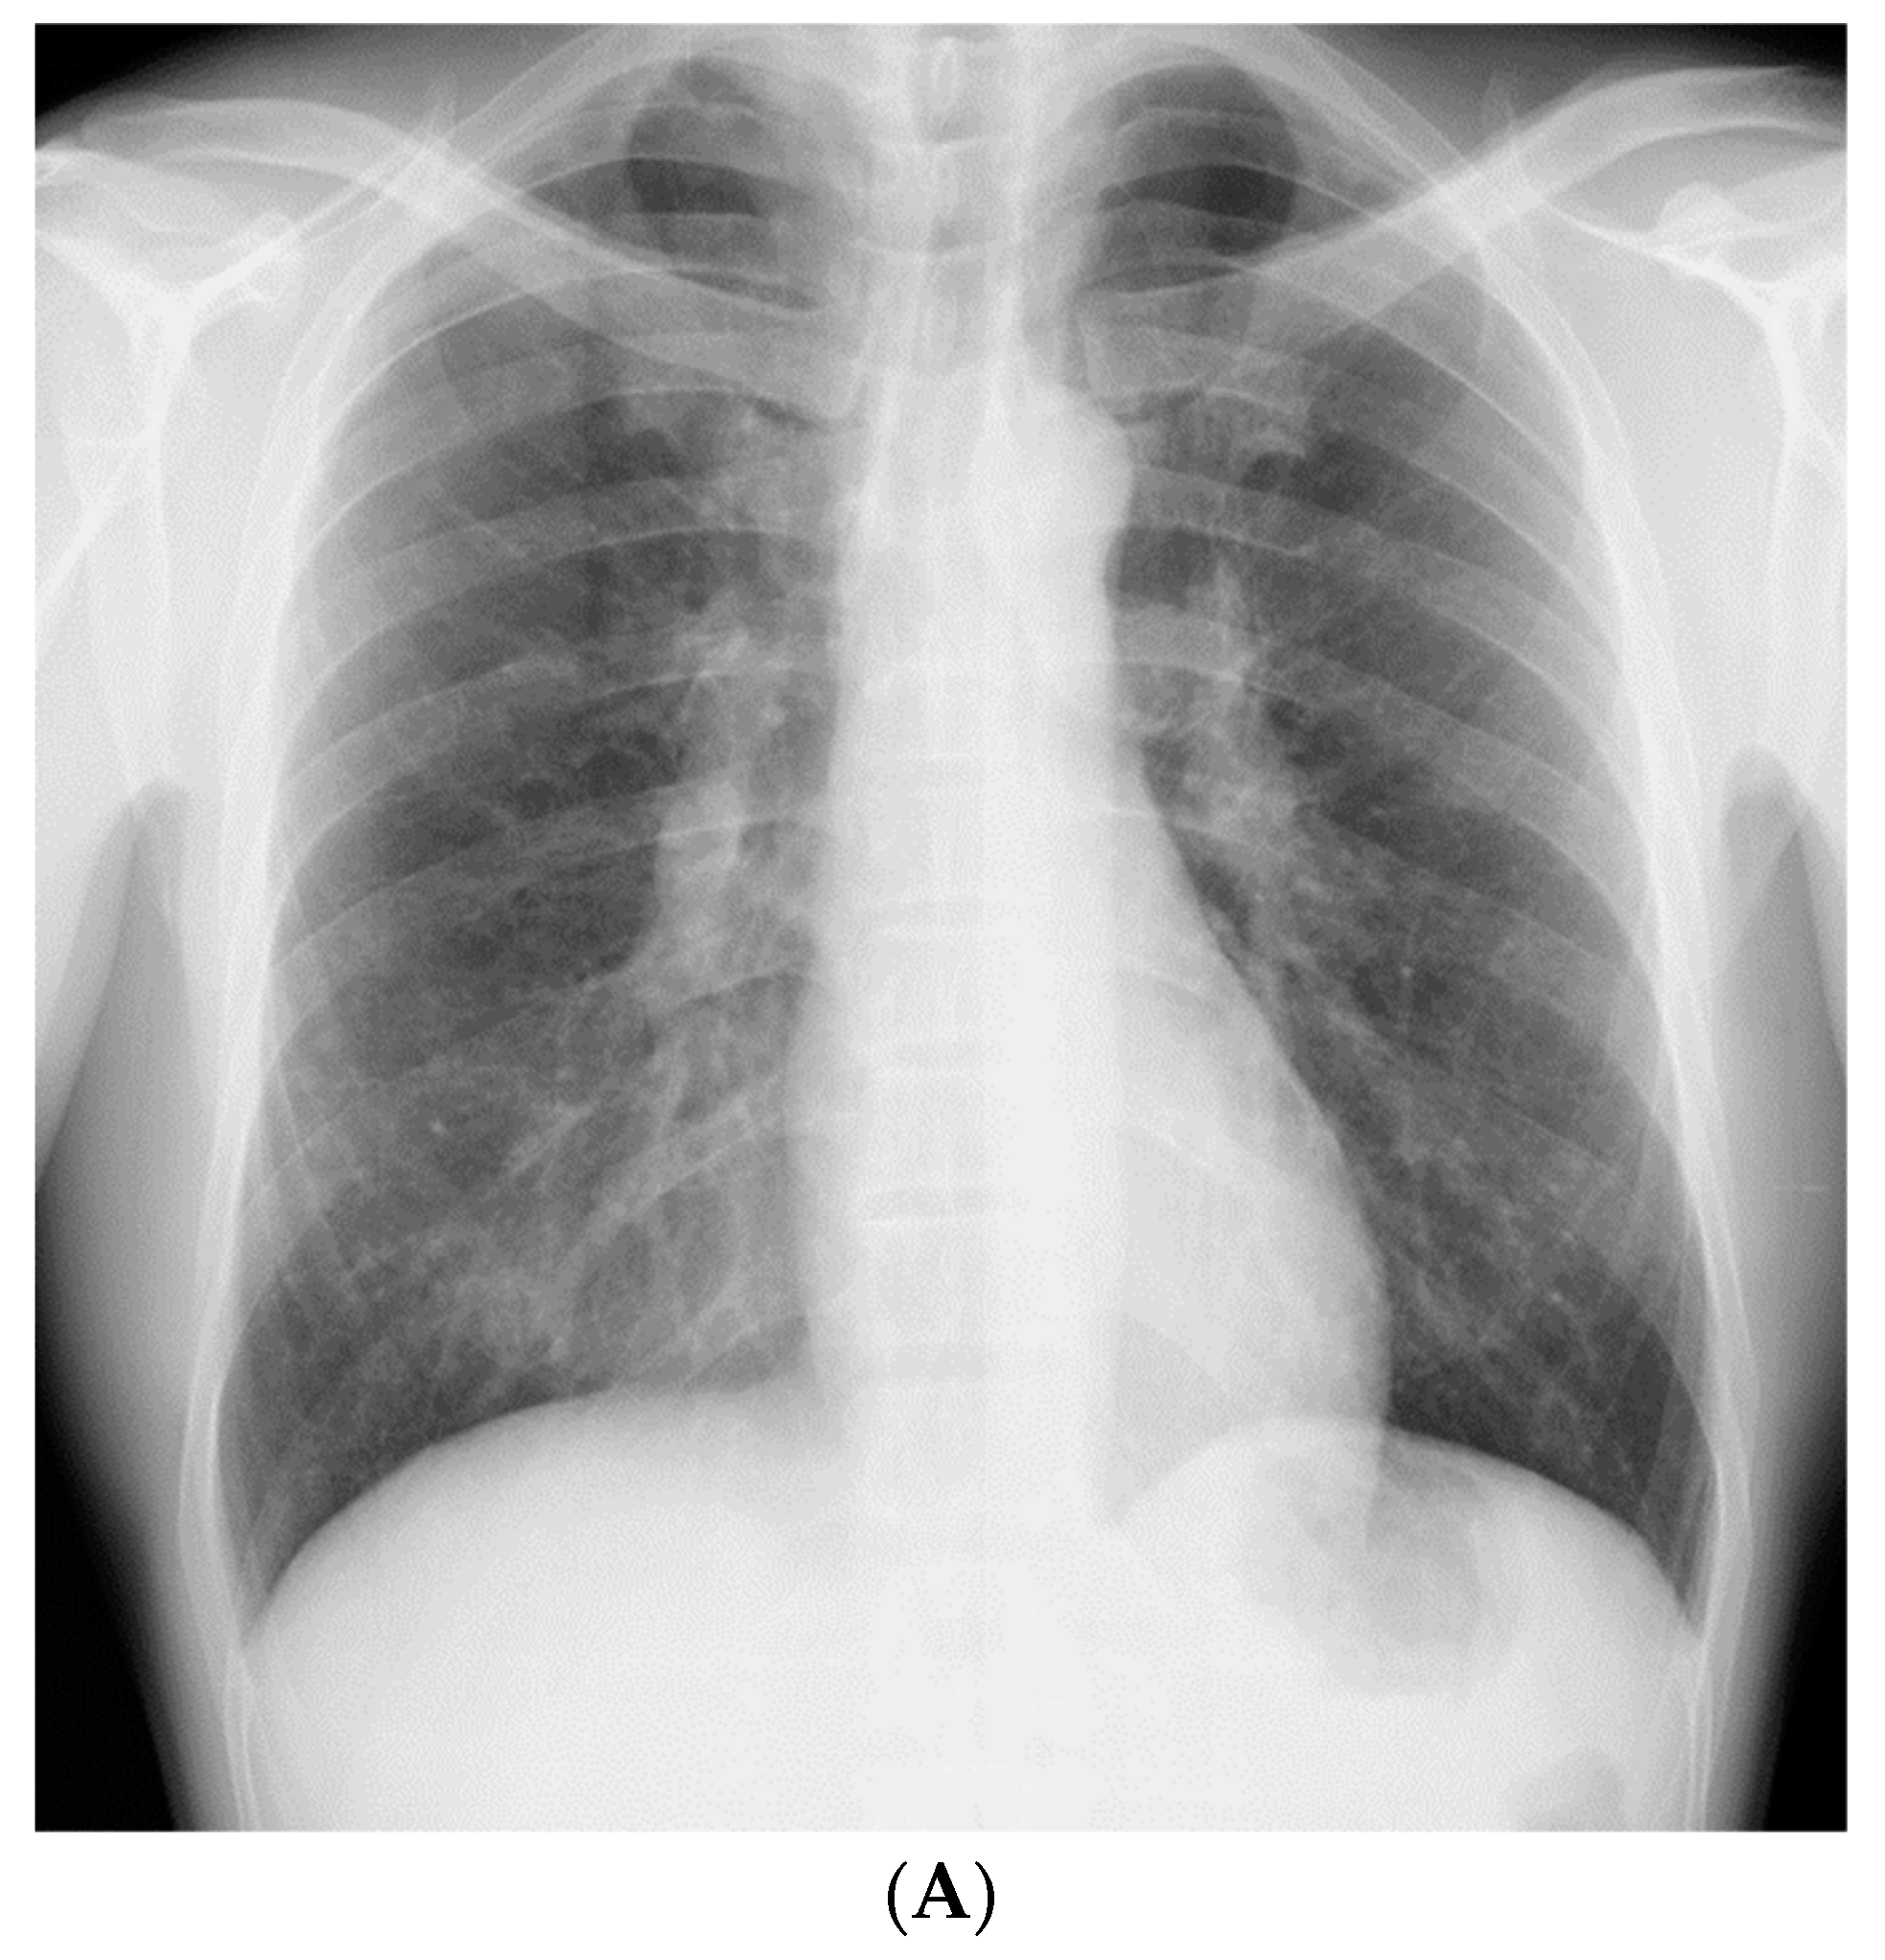

A 51-year-old, asymptomatic Japanese man with rapidly progressing nodular shadows, as observed on chest radiography performed as part of his routine physical examinations, was referred to our hospital. Two years ago, his chest radiograph had revealed no abnormalities. Small nodules had appeared a year later, mainly in both the lower lung fields (Figure 1A); however, he did not visit a hospital. Further, he reported a smoking history of 30 pack-years. As a civil engineer, he had been engaged in underground construction with welding, cutting, and drilling of reinforced concrete and metals for 10 years (between the ages of 41 and 51 years); though he had never used and/or been exposed to beryllium.

Figure 1.

(A) Chest radiograph 1 year prior to referral to our hospital, showing small nodules in both the lower lung fields. (B) Chest radiograph on admission, showing an increase in the number of nodules in 1 year.

The patient did not display clinical respiratory symptoms such as dyspnea, exercise intolerance, or any other relevant manifestations upon referral to our hospital. The patient’s body temperature, pulse rate, and respiratory rate were 36.9 °C, 58 beats/min, and 20 breaths/min, respectively. On chest auscultation, fine crackles were audible in the bilateral lower lung fields. Clubbed fingers were not observed. Laboratory data on admission revealed elevated levels of PR3-ANCA (15.4 U/mL, cutoff level: 3.5 U/mL). Other representative tests for collagen disease-related autoantibodies were negative. Serum levels of angiotensin-converting enzyme, carcinoembryonic antigen, KL-6, and sIL-2R were in the normal range, and the results of interferon-gamma release assay were negative. The chest radiograph on admission showed an increase in the number of nodules compared with those found 1 year previously (Figure 1B).